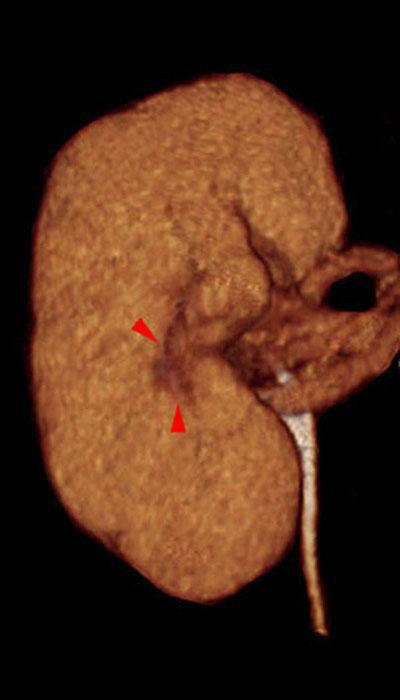

Nefrectomía parcial. Tumorectomia